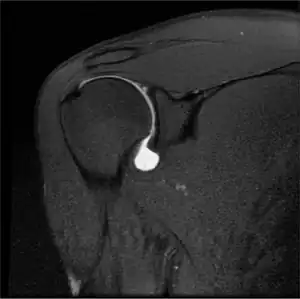

A SLAP tear is an injury to the glenoid labrum (fibrocartilaginous rim attached around the margin of the glenoid cavity in the shoulder blade). SLAP is an acronym for "superior labral tear from anterior to posterior".

Twelve varieties of SLAP lesion have been described, with initial diagnosis by MRI or arthrography and confirmation by direct arthroscopy.[6]